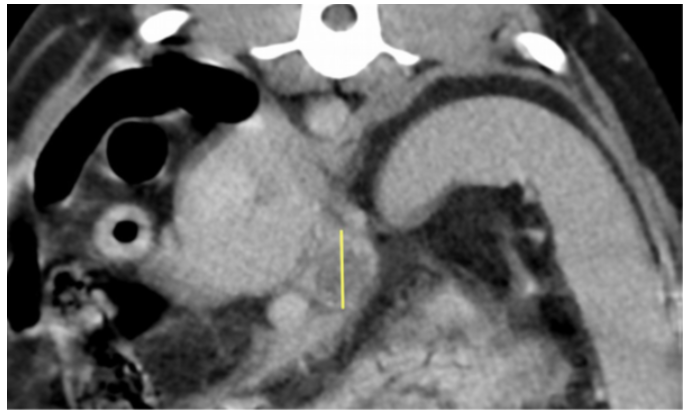

There was an approximately 4cm soft tissue mass located in the bladder trigone (Images 1 – 2). The mass dislocated the right ureter abaxially and dorsally, but was not causing obstruction. There was a large, approximately 7cm x 7cm x2cm parietal mass in the cranial wall of the gastric fundus. The mass protruded into the gastric lumen and was accompanied by an alteration of gastric wall layering (Image 3). A smaller mass was identified in the wall of the greater curvature of the stomach, measuring approximately 4cm x 1cm. The cranial abdominal lymph nodes were enlarged and hypoattenuating (Image 4). No other abnormalities were seen.

Image 4: Axial slice of a post-contrast scan showing an enlarged left hepatic/portal lymph node with hypoattenuation ( yellow line indicates extent of dorsoventral width).